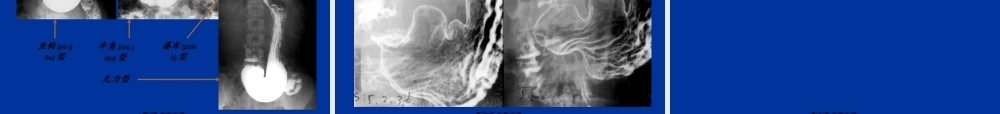

消化系统(xiāohuàxìtǒng)影像学第一页,共一百一十二页。普通检查腹部平片价值有限(yǒuxiàn)透视少用第二页,共一百一十二页。钡剂造影检查范围:上消化道全消化道结肠方法:1、常规法(粘膜相、充盈相、加压相)2、气钡双重造影显示细微结构3、小肠灌钡造影4、结肠造影(灌肠(guàn〃cháng)法、口服法)血管造影胃肠道出血CT第三页,共一百一十二页。造影(zàoyǐng)检查钡餐(bèicān)造影小肠(xiǎocháng)造影钡剂灌肠造影第四页,共一百一十二页。胃肠道CT检查(jiǎnchá)第五页,共一百一十二页。平片:显示阳性结石术后经T形管造影内镜逆行(nìxíng)性胰胆管造影(Endoscopicretrogradecholangio-pancreatography,ERCP)经皮肝穿胆管造影(Percutaneoustranshepaticcholangiography,PTC)CTMRI,MRCP第六页,共一百一十二页。X线检查价值有限CT:平扫增强(zēngqiáng):动脉期、门脉期;实质期MRI:平扫、增强、动态增强MRA第七页,共一百一十二页。平片第八页,共一百一十二页。口服(kǒufú)胆囊造影第九页,共一百一十二页。静脉(jìngmài)胆道造影第十页,共一百一十二页。ERCPPTCT管造影(zàoyǐng)第十一页,共一百一十二页。CT检查(jiǎnchá)第十二页,共一百一十二页。MRI检查(jiǎnchá)第十三页,共一百一十二页。第十四页,共一百一十二页。咽:会厌(huìyàn)梨状窝第十五页,共一百一十二页。轮廓光整管状影数条平行走行的粘膜皱襞四个狭窄食道入口处狭窄;主动脉弓压迹;左主支气管;横膈裂孔部狭窄膈壶腹胃食管前庭(qiántíng)蠕动波第十六页,共一百一十二页。食管(shíguǎn)第十七页,共一百一十二页。X线分区形态轮廓(lúnkuò)粘膜皱襞微皱襞胃小区胃小沟蠕动波第十八页,共一百一十二页。胃底胃角胃体胃小弯胃大弯第十九页,共一百一十二页。鱼钩(yúɡōu)型牛角(niújiǎo)型瀑布(pùbù)型无力型第二十页,共一百一十二页。胃粘膜、胃小区(xiǎoqū)、胃小沟第二十一页,共一百一十二页。十二指肠:"C"形球部框部空肠与回肠:分组结肠(jiécháng):结肠(jiécháng)袋无名沟无名区第二十二页,共一百一十二页。第二十三页,共一百一十二页。第二十四页,共一百一十二页。第二十五页,共一百一十二页。轮廓改变crater憩室充盈缺损(fillingdefect)粘膜改变破坏(pòhuài)平坦增宽纡曲纠集微粘膜皱襞改变管腔大小异常位置及可动性异常...